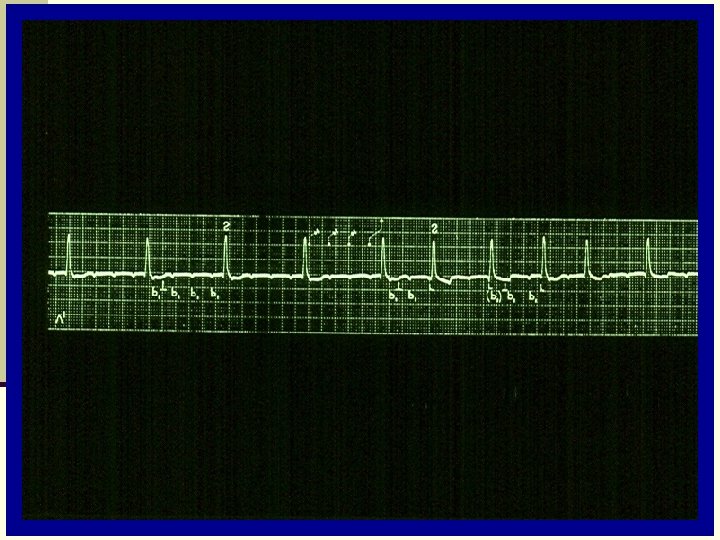

E C G: Biphasic P-wave atrial activation time is increased